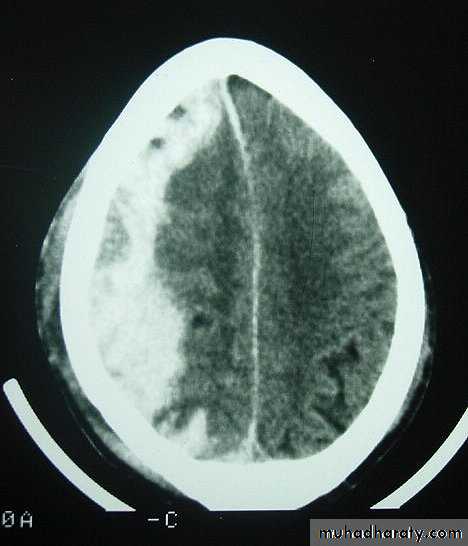

Clinical Picture: patient will present with a picture similar to that of an extradural haematoma, but there is persistent loss of consciousness with no lucid interval.Ct scan will show a concave hyperdence collection because blood follows the subdural space over the convexity of the brain.

Acute Subdural Haematoma